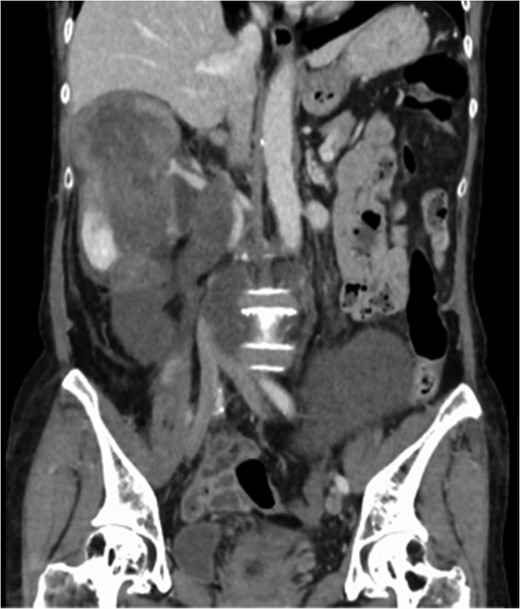

Multidetector CT scan (coronal view). The tumor invaded the IVC from the orifice of the right renal vein and the peripheral IVC was almost fully occluded.